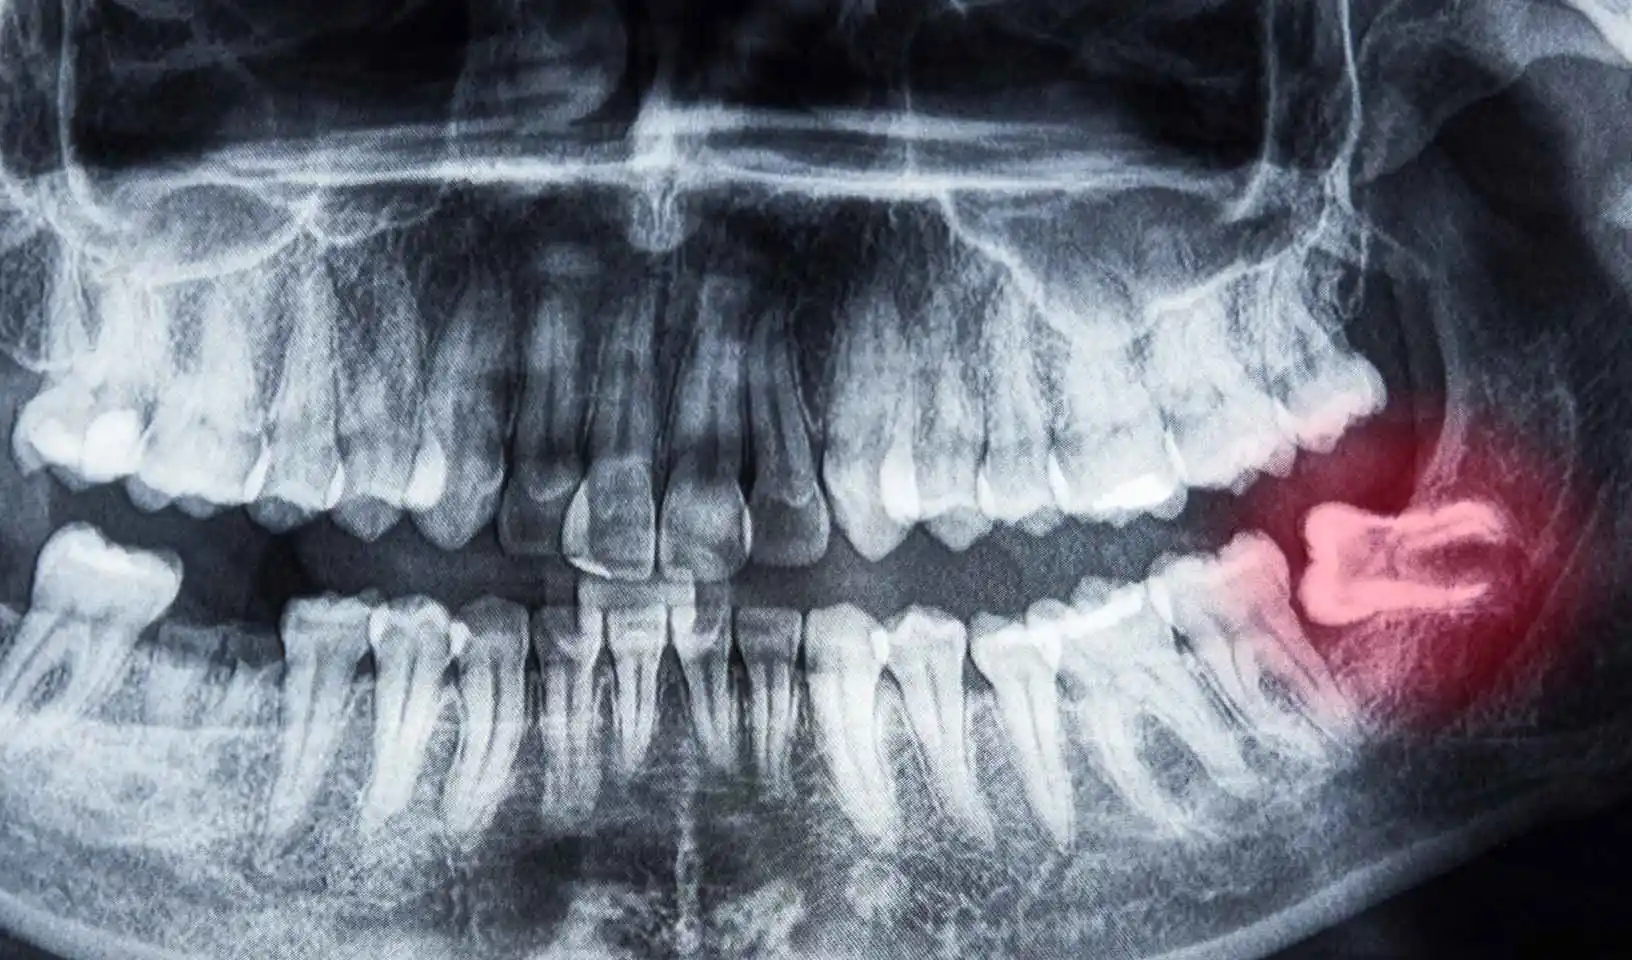

Vađenje umnjaka Novi Sad

Vađenje umnjaka je uobičajen zahvat oralnog hirurga koji se izvodi kada umnjak izraste i izazove bol ili neprijatnost u vilici. Umnjaci su poslednji zubi koji rastu u vilici, a često su problematični zbog nedovoljnog prostora za njihov rast. Kada se pojave problemi sa umnjacima, kao što su bol, otok, infekcija ili nepravilan rast, oralni hirurg će najčešće preporučiti vađenje umnjaka. Sam zahvat se obično izvodi pod lokalnom anestezijom i traje samo nekoliko minuta. Nakon vađenja umnjaka, pacijenti mogu osetiti blagu nelagodnost i otok, ali će se to smanjiti nakon nekoliko dana.

Važno je da znate da postoje komplikovane procedure vađenja umnjaka, koje su iskusnom i stručnom hirurgu rutinske, dok mnogim stomatolozima i hirurzima mogu da predstavljaju značajan izazov. Da biste izbegli komplikacije, važno je da Vas pregleda i zahvat izvrši dobar stručnjak.